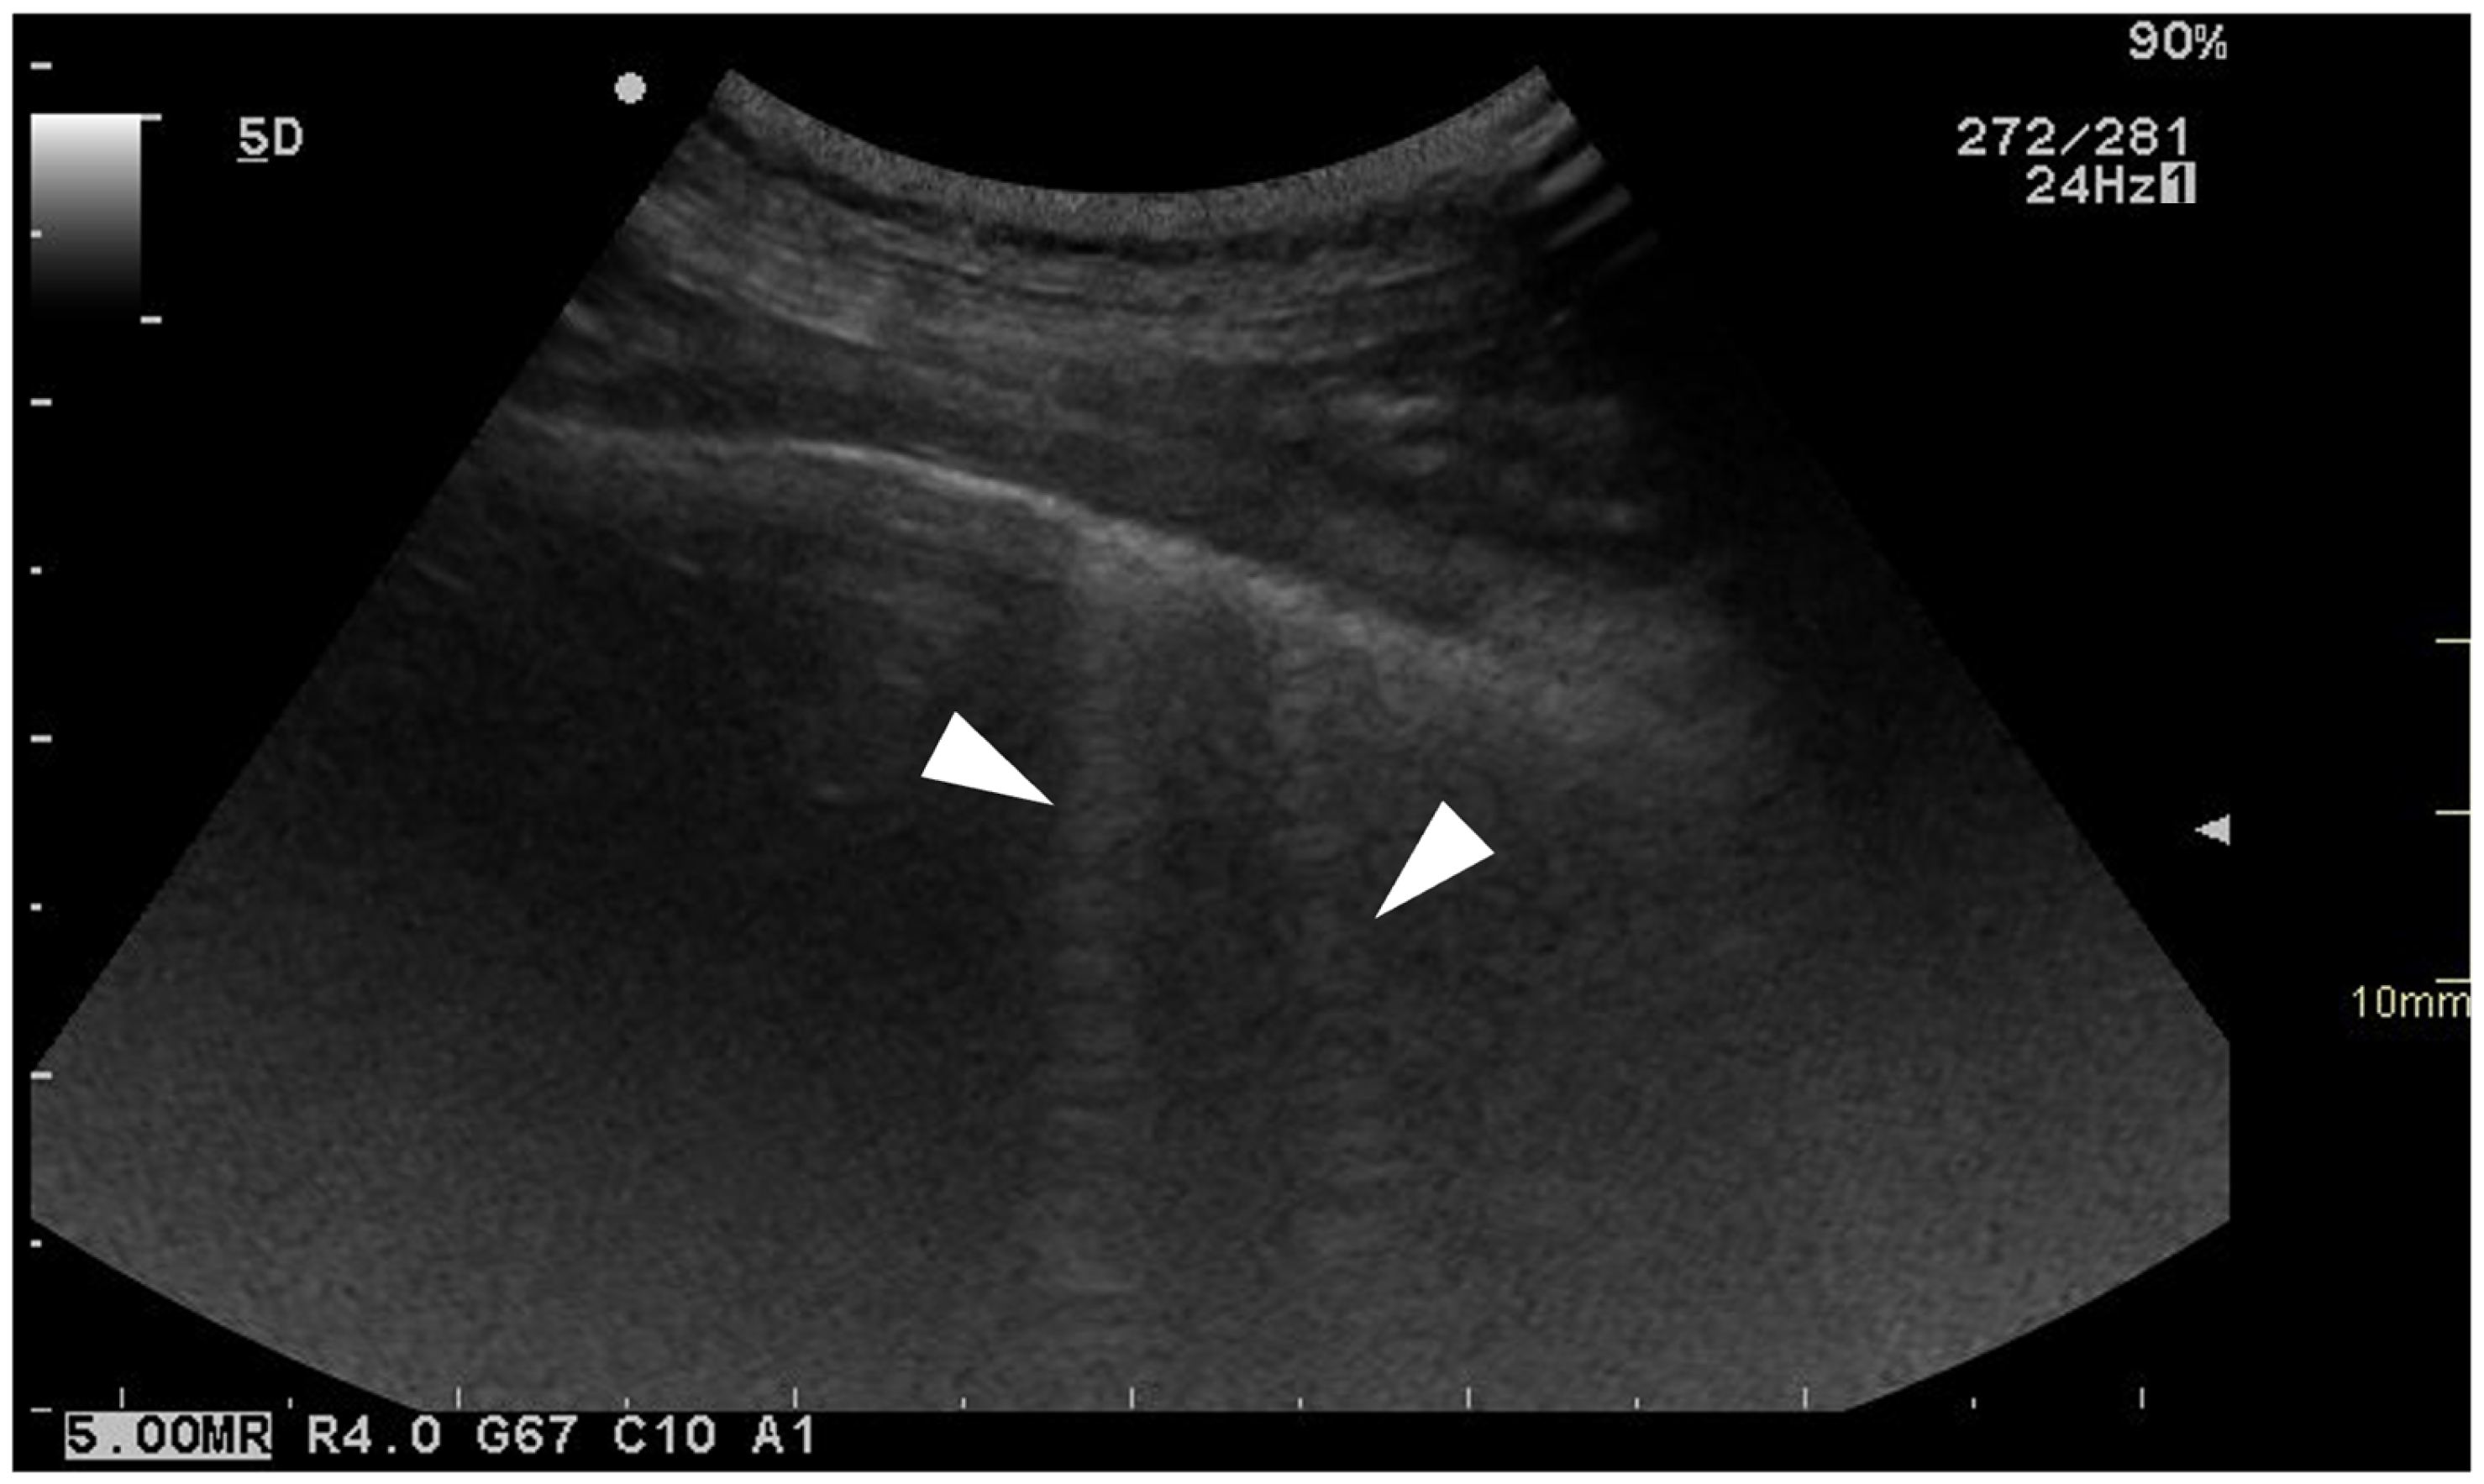

3.3.4. Pleural Surface